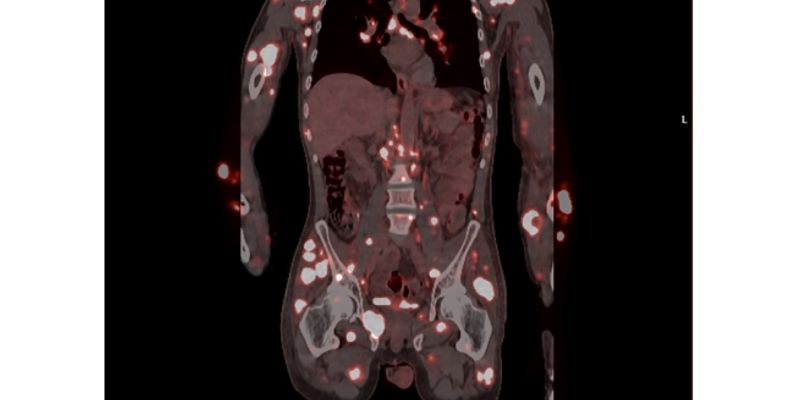

本文报告一例罕见的IDH突变型4级星形细胞瘤年轻患者,其肿瘤伴有原始神经外胚层成分并迅速发生全身骨转移。文章深入探讨了此类侵袭性肿瘤的分子特征、转移机制,并强调了全面分子检测对于指导治疗(如IDH抑制剂)的重要性。了解最新诊疗进展,为患者寻求更多希望。 Read More... "警惕!IDH突变4级星形细胞瘤罕见全身转移病例分析与治疗新方向"